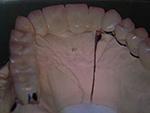

Die folgenden Patientenfälle sollen Ihnen einen Einblick in die Möglichkeiten der modernen Implantation geben.

Komplett-Implantation: